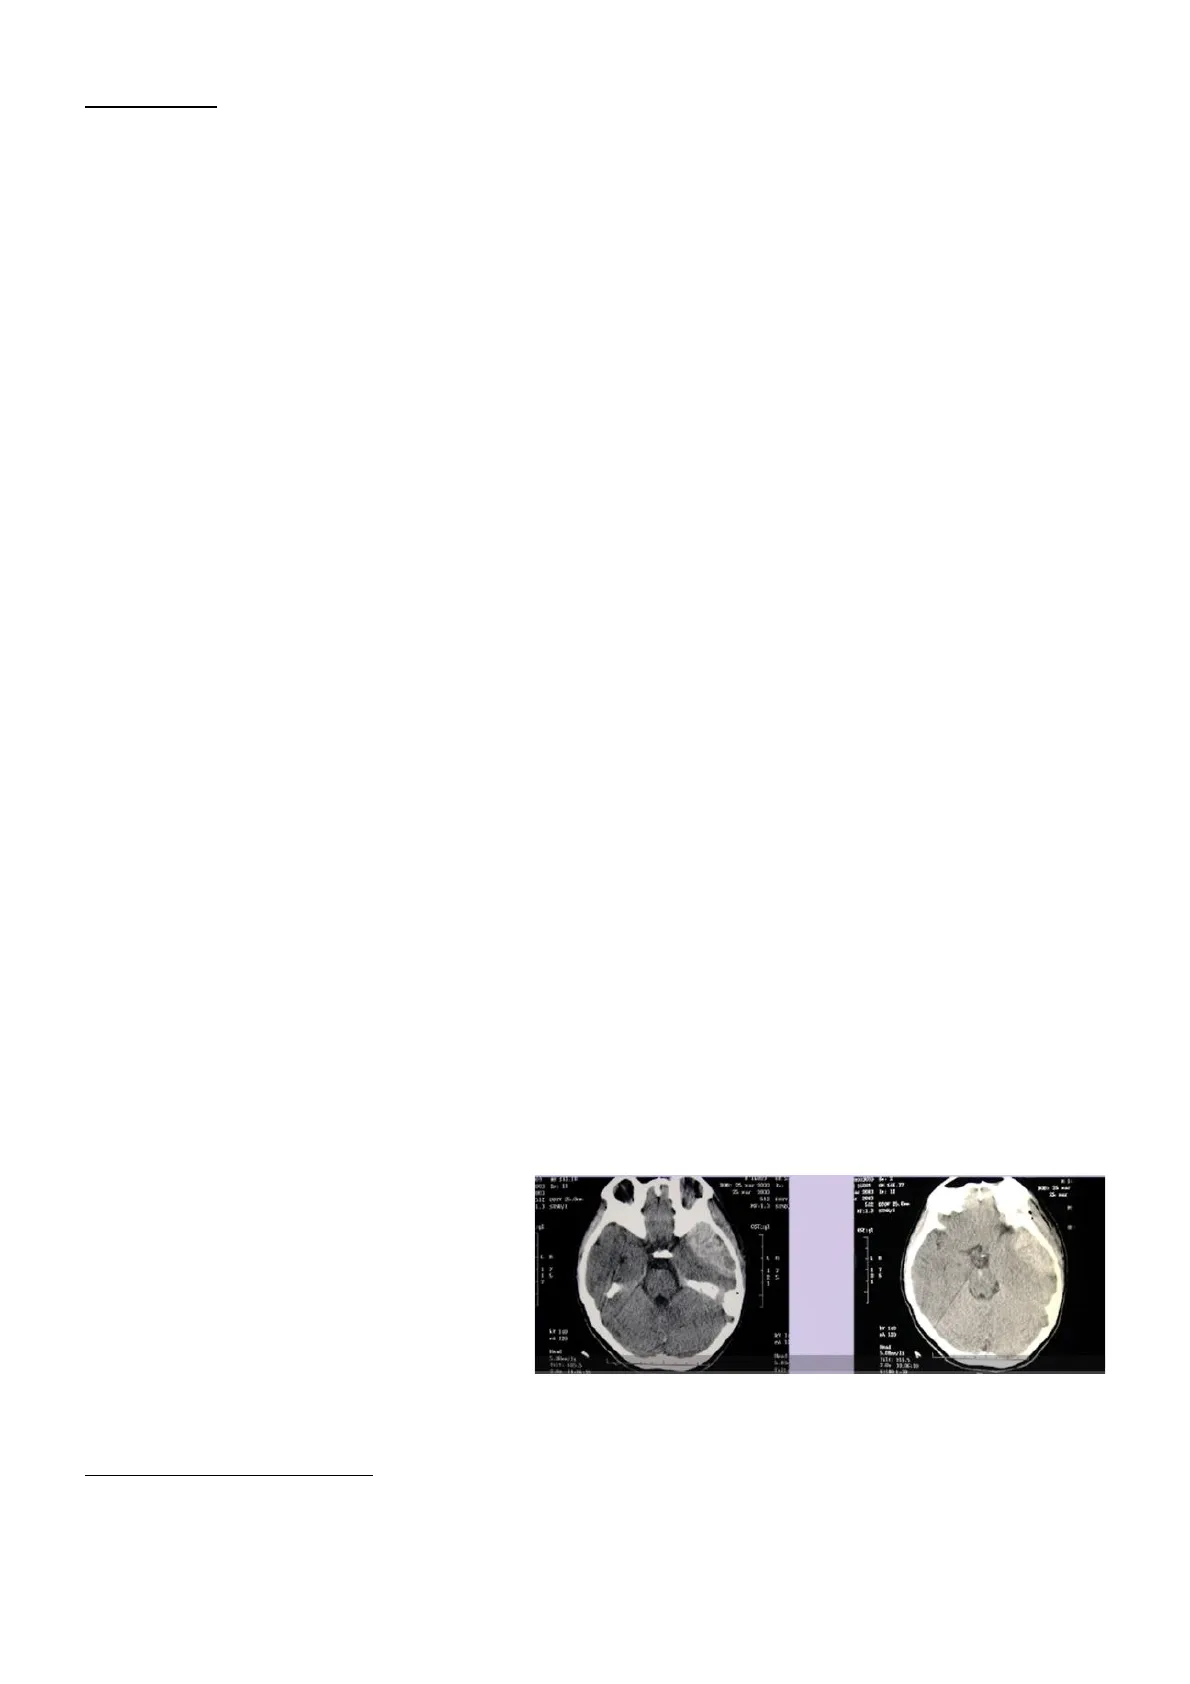

Nel caso di un paziente con una grossa massa all'interno del cervelletto, quest'ultimo si sposterà verso il forame occipitale e verso l'incisura tentoriale e quindi ernierà nello spazio vicino, che però non gli compete. Comprimerà in tal modo delle strutture, dando una sintomatologia clinica che il medico dovrà riconoscere da un punto di vista neurologico. Il tentorio è posto orizzontalmente nella scatola cranica e definisce lo spazio sopratentoriale (cervello) e lo spazio sottotentoriale (cervelletto e tronco cerebrale), mentre la falce cerebrale divide lo spazio sopratentoriale in due metà (emisferi). Lo spazio sottotentoriale comunica in alto, attraverso la fessura del tentorio, con lo spazio emisferico e in basso, attraverso il forame magno cerebrale, con lo spazio rachideo.

La scatola cranica è divisibile in tre compartimenti che sono collegati ad un quarto, sottostante rispetto ad essa: emisferico destro, emisferico sinistro e fossa posteriore. Un processo di tipo espansivo che dovesse interessare inizialmente uno di questi compartimenti, creerebbe un aumento di pressione localizzato e di conseguenza un gradiente pressorio da questo al compartimento vicino, con la tendenza a spostare parte del contenuto cerebrale. Questo è alla base delle ernie cerebrali interne.